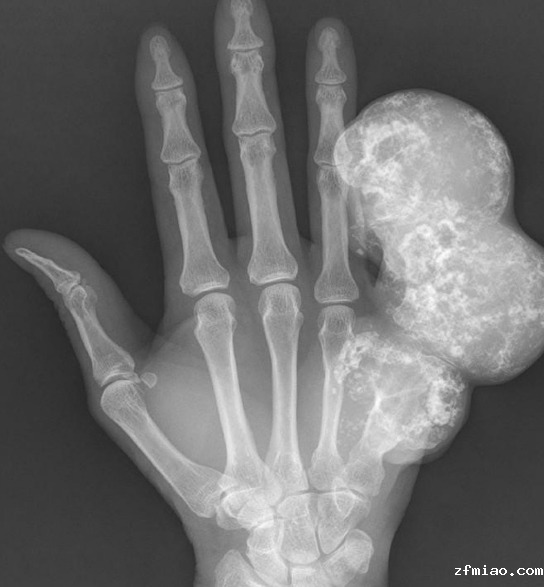

骨密度检测仪器提醒软骨内瘤是一种发生在骨中的良性骨肿瘤。它通常没有症状,或伴有轻度疼痛和无痛肿胀,看起来更像肢体局部肿胀,生长缓慢,多年来体积没有明显变化。目前手术后,黄先生的左手恢复良好。